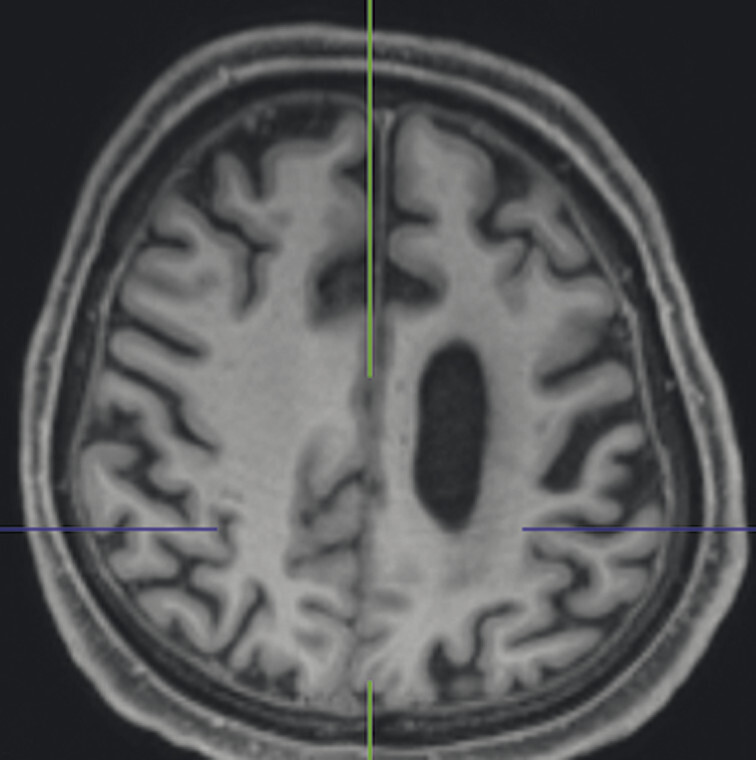

Abb. 69.10 Parkinson-Syndrome: Differenzialdiagnose progressive supranukleäre Parese mit Parkinson-Syndrom.

74-jähriger Patient mit linksbetontem Parkinson-Syndrom und aktuell deutlicher demenzieller Entwicklung mit exekutiver Störung und Zeitgitterstörung. In der T1w 3-D-MRT zeigt sich ein unauffälliges Mesenzephalon (a) mit einer normalen Midbrain/Pons-Ratio von 0,61 (kurzer Durchmesser des Mesenzephalons: 9,9 mm; kurzer Durchmesser des Pons: 16,1 mm, beide durch eine rote Linie dargestellt; b). Die automatisierte Ganzhirnvolumetrie (c) lässt außerdem ein anomales Hirnvolumen frontal bis parietal beidseits erkennen. In der 2 mm dünnen transversalen SWI-Schicht findet sich kein Schwalbenschwanzzeichen (d).

a T1w 3-D-MRT-Sequenz.

b T1w 3-D-MRT-Sequenz mit eingezeichneten Durchmessern.

c Ganzhirnvolumetrie.

d Transversale SWI.